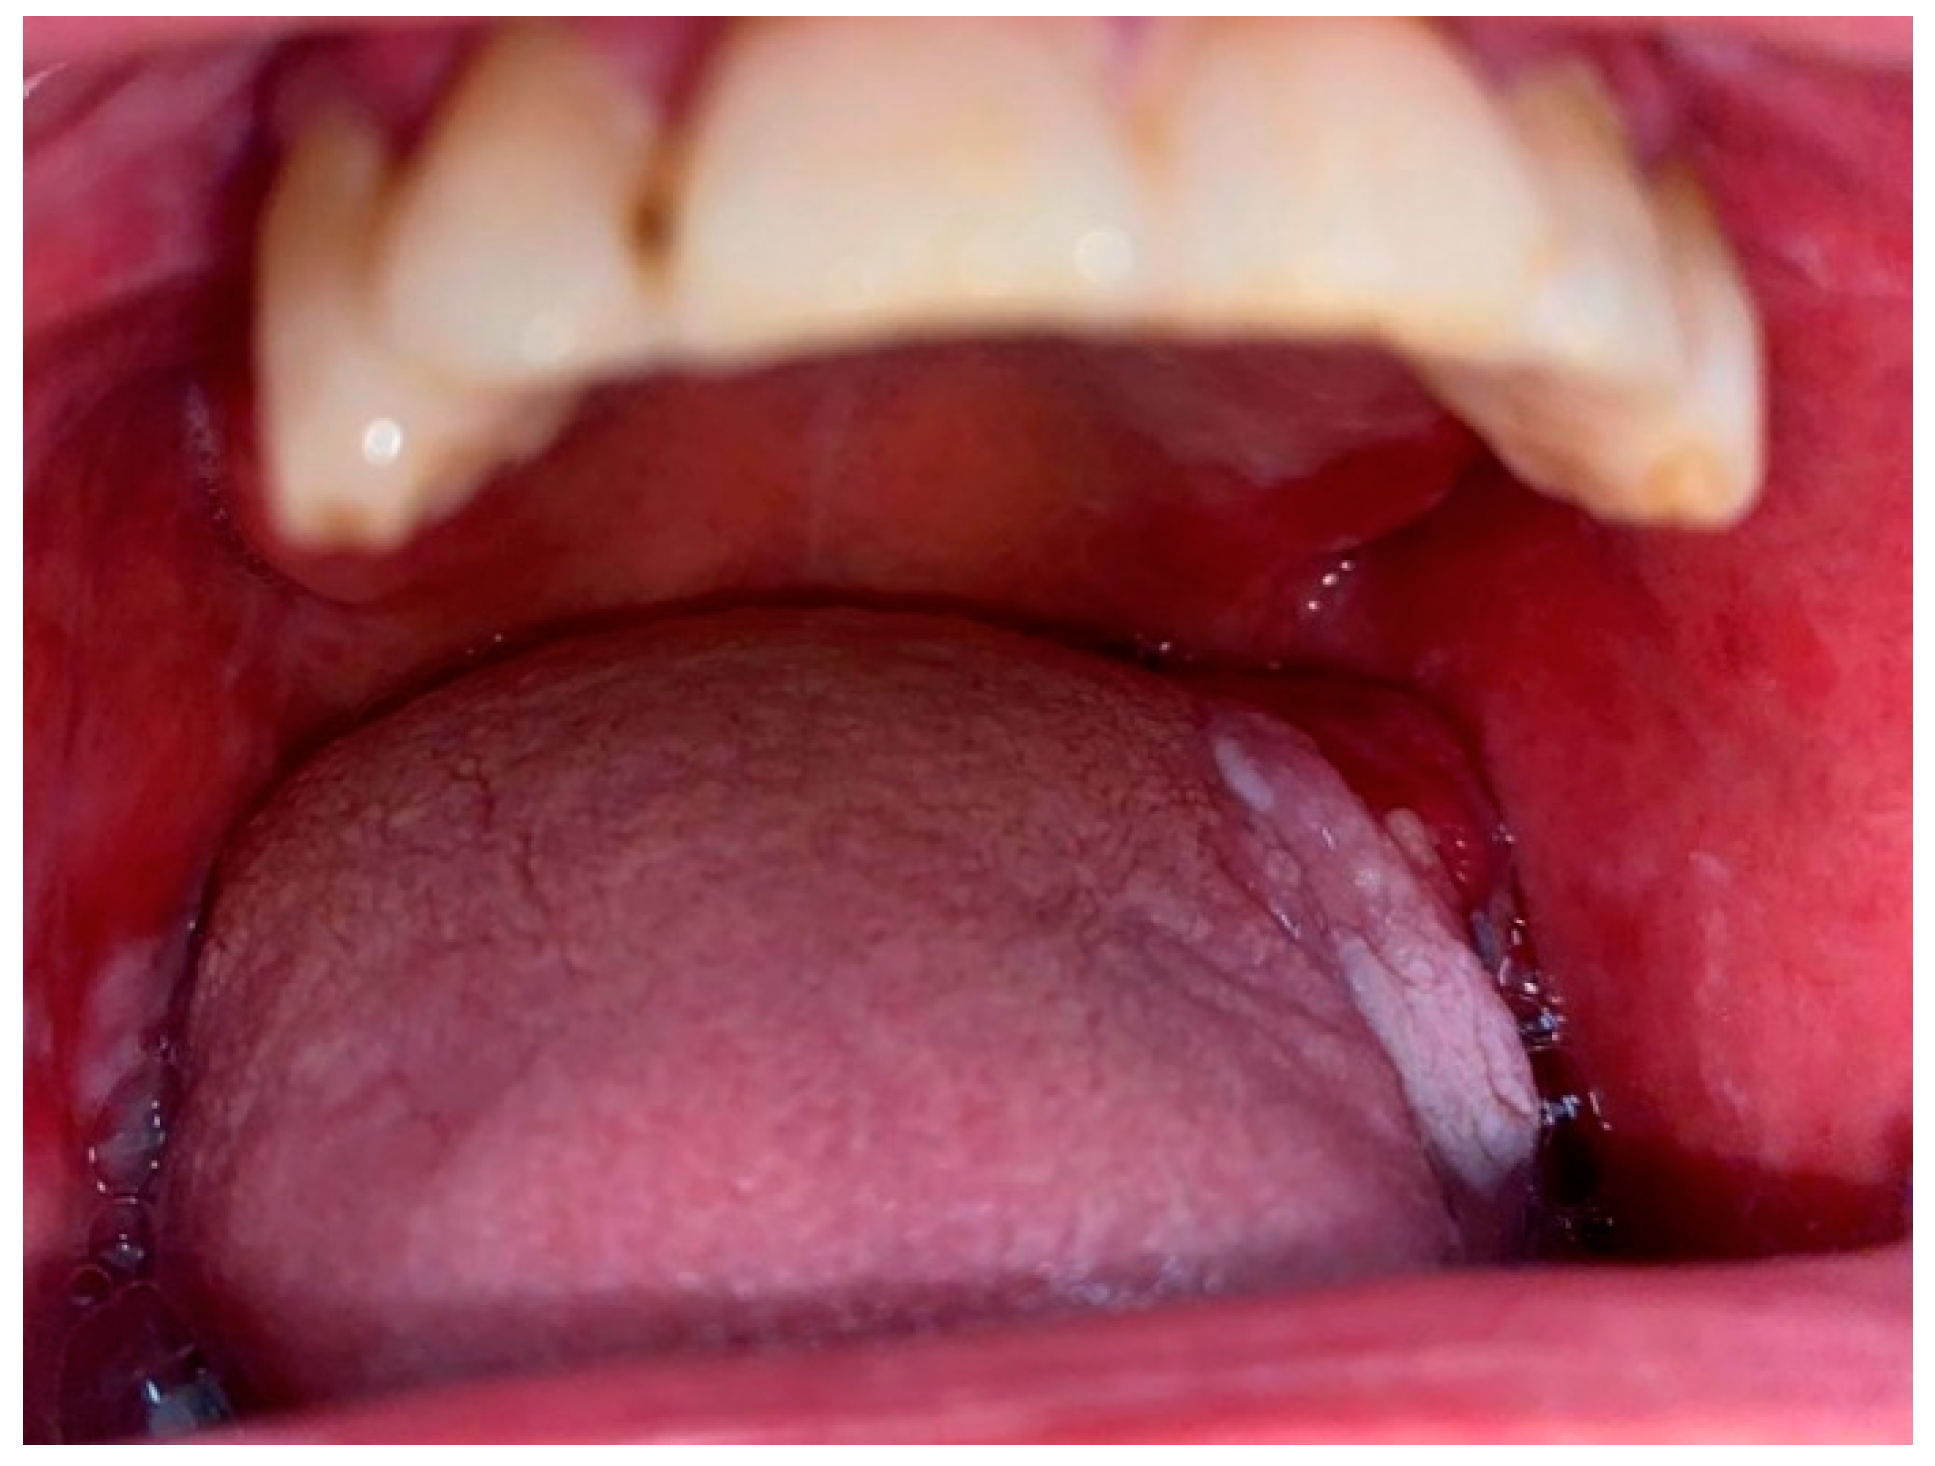

2.1. Oral Leukoplakia, Proliferative Verrucous Leukoplakia and Erythroplakia

2.3. Submucosal Fibrosis